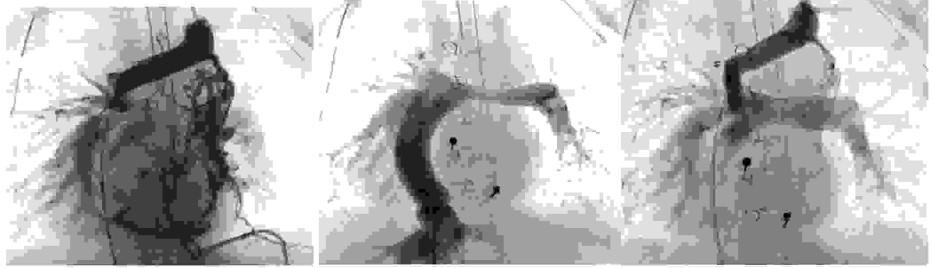

Pytanie 90

Na podstawie poniższych obrazów angiograficznych wskaż prawidłowe rozpoznanie oraz zastosowaną metodę leczenia: